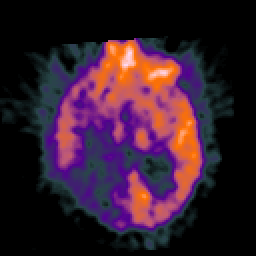

Glioma Overlay -- Slice #10

[Home][Help][Clinical] Slice 10